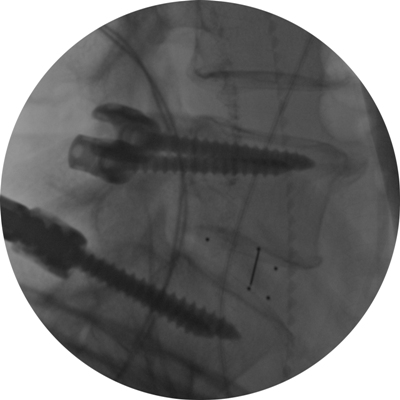

Astfel, în urma unui număr mare de investigaţii suplimentare, a fost luată decizia de a folosi un abord chirurgical numit ”fuziune intervertebrală transforaminală”. Tehnica dată este mai complicată şi mai solicitantă faţă de dotarea tehnică a blocului de operaţii şi a abilităţilor echipei chirurgicale, însă oferă un şir de avantaje pentru pacient.

Deoarece pacientul a fost operat anterior de 2 ori, utilizarea aceluiaşi coridor chirurgical tradiţional putea fi însoţită de un risc mare de leziuni a nervilor şi vaselor în canalul spinal. De aceea, a fost aleasă o cale mai puţin utilizată în practica cotidiană, dar care a fost cea mai raţională pentru pacientul dat, aşa-numitul abord paramedian transmuscular sau abordul prin spaţiul Wiltse.

Este un caz fericit pentru pacientul din Italia şi de succes pentru secţia Neurochirurgie, dar şi pentru întreaga instituţie medicală, or, astfel de intervenţii complicate au devenit posibile în Republica Moldova în urma deschiderii noului Bloc chirurgical în luna mai curent, prin intermediul căruia ţara noastră a obţinut facilităţi şi posibilităţi care au existat pînă nu demult doar în centrele medicale contemporane performante din lume. Astfel, sala de operaţii Hybrid a blocului dispune de metode de neuroimagistică intraoperatorie şi sisteme de monitoring şi neuronavigaţie, sisteme specializate de implanturi din titan şi instrumente chirurgicale, echipamente pentru disecţie osoasă. Acest complex chirurgical este completat de un departament ultradotat de anestezie şi neuroreanimare, care asigură o parcurgere perioperatorie fără complicaţii.